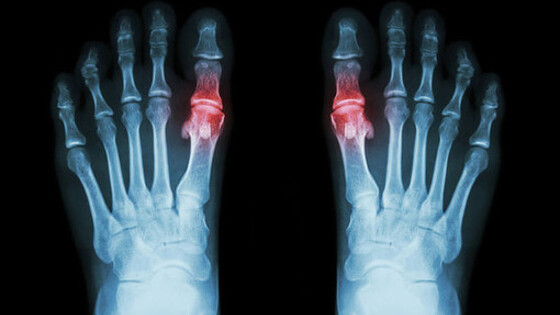

Исследователи из Ноттингемского университета вместе с коллегами из Кильского университета (Великобритания) обнаружили, что риск сердечного приступа и инсульта временно увеличивается в течение четырех месяцев после обострения подагры. Результаты опубликованы в журнале JAMA. Команда использовала медицинские данные 62 574 пациентов с подагрой, содержащиеся в Национальной службе здравоохранения Великобритании. Ученые обнаружили, что у многих пациентов с подагрой, перенесших сердечный приступ или инсульт, часто наблюдался приступ подагры за 60 дней до приступа. У пациентов с подагрой, которые умерли из-за инфаркта или инсульта, вероятность наличия приступа подагры в предшествующие 60-120 дней в 2-4 раза выше, чем у остальных пациентов. Это исследование показаывает важность длительной терапии пациентов с подагрой препаратами на основе аллопуринола, противовоспалительными лекарствами и соблюдения специальной диеты. Подагра — это распространенная форма артрита, которая вызывается высоким уровнем мочевой кислоты, откладывающейся в суставах и вокруг них в виде игольчатых кристаллов. Их разрушение приводит к сильному воспалению в течение 1-2 недель, которое сопровождается сильным отеком, покраснением и болезненностью. От подагры страдает 1 из 40 взрослых людей в Великобритании.